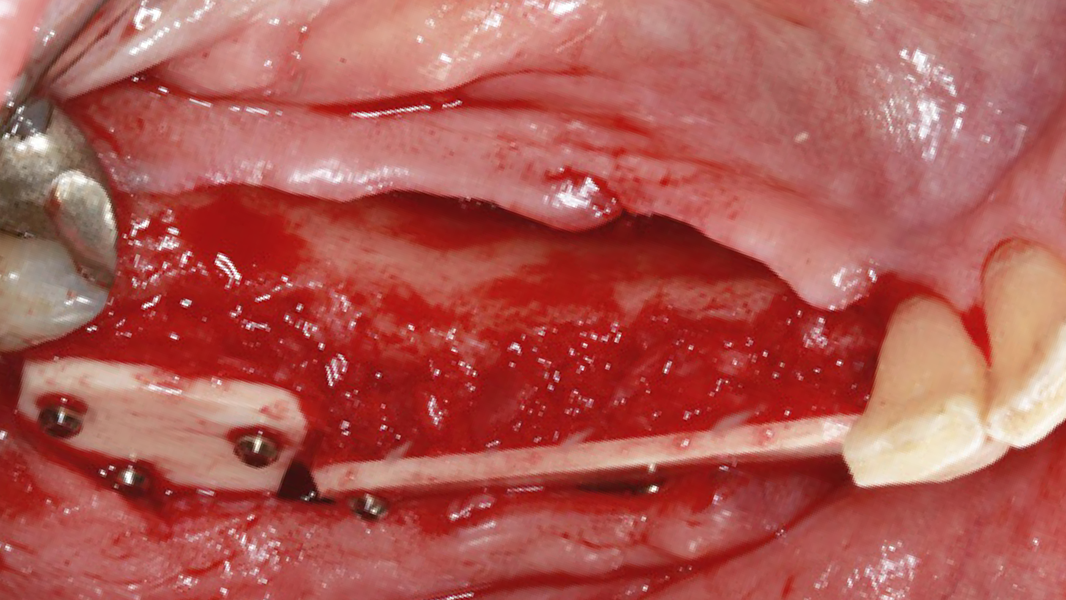

Die rein spongiösen Granulate ermöglichen durch eine zügige Remodellierung einen schnellen Knochenaufbau bei eingegrenzten Defekten, wohingegen das kortiko-spongiöse Material beim Aufbau ausgeprägter knöcherner Defekte für eine längere Volumenstabilität sorgt.

Wird Natriumhyaluronat dem Knochenersatzmaterial hinzugefügt, ermöglicht es bei Flüssigkeitszufuhr eine mühelose Bereitung von „Sticky Bone“, wodurch die Handhabung des Knochenersatzmaterials bei der Applikation in situ verbessert wird.14, 15

Klinische Erfahrungen MinerOss A + HYA